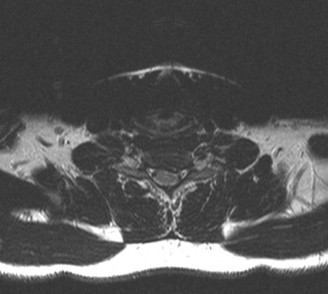

Magnetic Resonance Imaging and the Posterior Ligamentous Complex

To definitively assess the integrity of the soft tissue stabilizers and the neural elements, a Magnetic Resonance Imaging (MRI) scan without contrast was performed. Historically, textbooks propagated the "50-50-25 rule," suggesting that a burst fracture was inherently unstable if it exhibited >50% canal compromise, >50% loss of vertebral body height, or >25 degrees of kyphosis. Modern spine trauma surgery has largely debunked this rigid radiographic dogma. We now understand that these bony metrics alone do not dictate mechanical instability. The true arbiter of stability is the Posterior Ligamentous Complex (PLC).

The MRI, particularly the Short Tau Inversion Recovery (STIR) and T2-weighted sagittal sequences, provided the definitive diagnosis. The images demonstrated profound hyperintensity and discontinuity of the ligamentum flavum, the interspinous ligaments, and the supraspinous ligaments at the T12-L1 level. The facet joint capsules were also disrupted, indicated by fluid within the joints. This complete failure of the PLC means the posterior tension band is gone. Regardless of the bony parameters, this spine cannot resist physiological flexion loads. If treated non-operatively, this injury will inevitably lead to progressive kyphosis, delayed neurological deficit, and intractable pain.